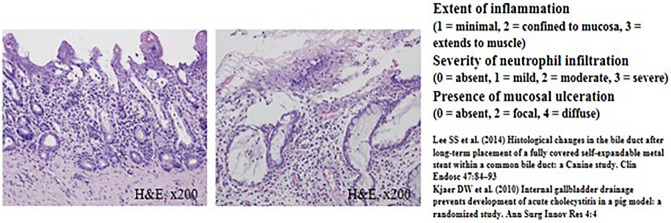

Macroscopic and microscopic histopathological evaluation

The common bile duct (CBD) diameter was 2.5 ± 0.5 mm in macroscopic findings. The biliary stricture length measured after harvesting of experimental animals was 36 mm ± 0.5 mm in macroscopic findings. Using H&E-stained tissue sections, the degree of histological damage was compared by examining the depth of inflammation, the degree of deposition of neutrophils, the presence of mucosal ulceration, and the overall score (Figs. 4, 5 and Tables 1, 2). The total histological score indicating histological damage of plastic stents was observed to be higher for the 3-month point than that for the 1-month point total score, median (range) of 1-month pigs vs. 3-month pigs: 6 (6–8) vs. 6.5 (6–8), although their difference was not statistically significant (p = 0.057) (Fig. 4 and Table 1). However, in the animal group in which the plastic stents were mounted for 5 months, the total score was observed to be significantly higher than those mounted for less time (total score, median (range) of 3-month pigs vs. 5-month pigs: 6.5 (6–8) vs. 9 (9–9), p = 0.029) (Fig. 5 and Table 2). The degree of tissue damage was compared using immunofluorescent staining (Fig. 6). From the top to the bottom, photomicrographs of H&E, Masson Trichrome staining, and immunofluorescence staining using CK 19 are shown. H&E staining revealed that the deposition degree of neutrophils of the tissue in the contact area of the plastic stents (Fig. 6). When the same area was observed after Masson Trichrome staining, extensive fibrosis of the tissue in the contact area was observed. At the bottom of Fig. 6, the immunofluorescent staining was performed using CK 19 for histologic evaluation.

In this study, we performed H&E staining, Masson Trichrome staining, and immunofluorescence staining (CK 19) to achieve an objective histopathological evaluation. Furthermore, the veterinarian pathologist in the animal laboratory evaluated and calculated the histological score based on the histological scoring system shown in Supplementary Table 1 commonly used in previous studies13–15. Histological damage caused by plastic stents was found to be higher when the follow-up time was longer. Interestingly, the total histologic score did not show any significant differences between different time points less than 3 months after inserting biliary plastic stents. However, at 5 months after stent insertion, a statistically significant difference in histological score was observed compared to that at shorter follow-up. Considering our results and cost effectiveness of the animal study, 1-month point after RFA seems to be the best timing for testing the new devices in the BBS in vivo swine models. Therefore, in clinical practice, it is recommended to remove the plastic stent between 3 and 6 months, which is the average patency period in previous studies16–18 to avoid histological damage.

Histopathological examination and evaluation

Pigs were euthanized at 1 month, 3 months, and 5 months after biliary plastic stents were inserted. Histopathological examination was then performed. After the liver, biliary tract, gallbladder, and duodenum were removed from experimental animals, a large amount of KCl (Potassium Chloride) was injected to induce euthanasia. From the extracted liver, biliary tract, gallbladder, duodenum, and AoV were dissected to the proximal end of the plastic stent located in the right and left intrahepatic bile duct. After the dissection, an incision was made in the longitudinal direction to confirm the proximal intrahepatic bile duct and distal biliary duct stenosis. The bile duct tissue was incised from the intrahepatic bile duct into which different plastic stents had been inserted and cut into sections, followed by H&E staining and Masson Trichrome staining. Histopathological examination was performed to reinforce the histological scoring method of previous studies. Scoring was performed in a blinded method using H&E-stained tissue sections. All sections were classified according to the extent of inflammation (1) (1, minimal; 2, confined to mucosa; and 3, extended to muscle with neutrophil infiltration). The severity of neutrophil infiltration was scored (2) as 0 for Absent, 1 for Mild, 2 for Moderate, and 3 for Severe. The presence of mucosal ulceration (3) was scored as 0 for Absent, 2 for Local, and 4 for Diffuse (Supplementary Table 1)13–15. Based on the histological scoring system shown in Supplementary Table 1, the histological score was calculated by a veterinarian pathologist in the animal laboratory of Samsung Life Sciences Research Institute.